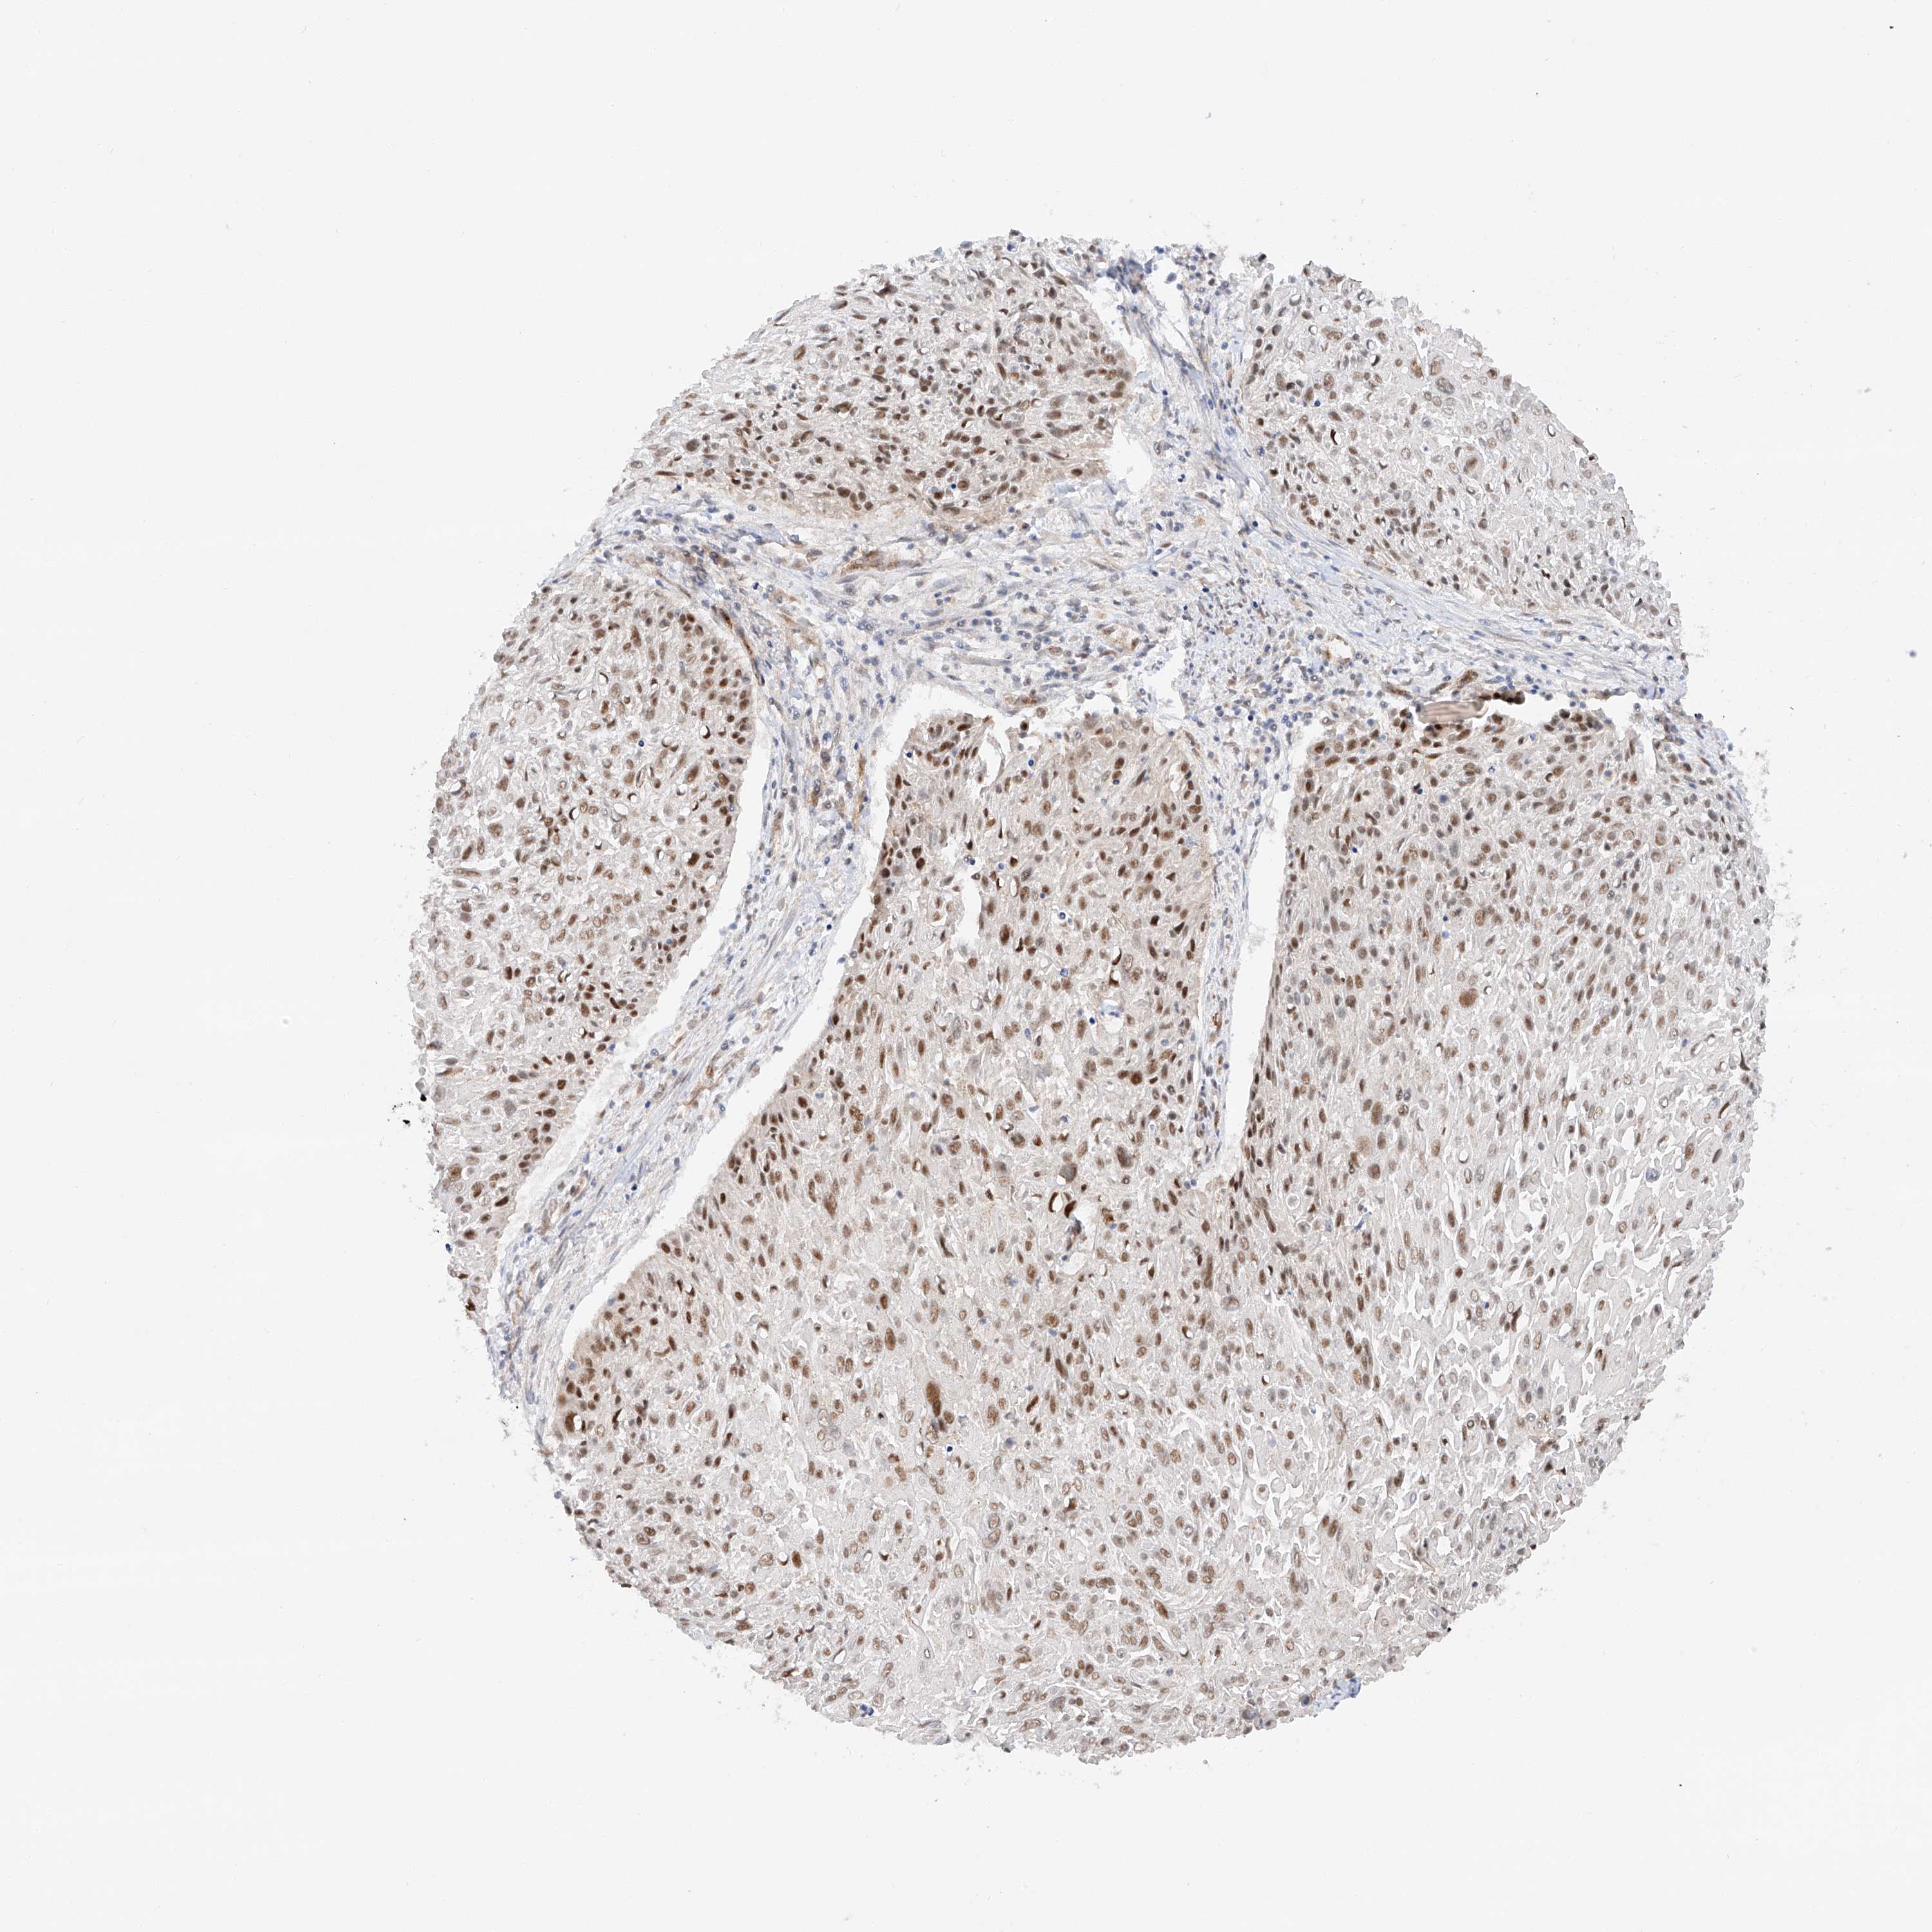

CERVICAL CANCER - Protein expressioni

A mouse-over function shows sample information and annotation data. Click on an image to view it in a full screen mode. Samples can be filtered based on level of antibody staining by selecting one or several of the following categories: high, medium, low and not detected. The assay and annotation is described here.

Note that samples used for immunohistochemistry by the Human Protein Atlas do not correspond to samples in the TCGA dataset.

Antibody stainingi

Antibody staining in the annotated cell types in the current human tissue is reported as not detected, low, medium, or high, based on conventional immunohistochemistry profiling in selected tissues. This score is based on the combination of the staining intensity and fraction of stained cells.

Each image is clickable and will lead to virtual microscopy that enables deeper exploration of all samples and also displays staining intensity scores, fraction scores and subcellular localization as well as patient and tissue information for each sample.

Antibody HPA031630

Staining

High

Medium

Low

Not detected

Intensity

Strong

Moderate

Weak

Negative

Quantity

>75%

75%-25%

<25%

None

Location

Nuclear

Cytoplasmic/membranous

Cytoplasmic/membranous,nuclear

Squamous cell carcinoma, NOS

Adenocarcinoma, NOS